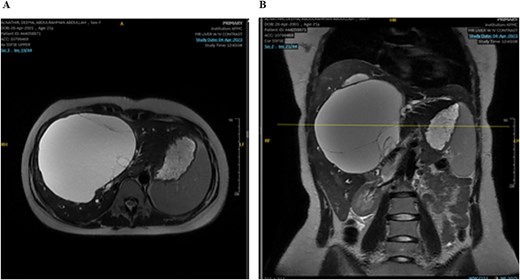

The mass had fine, minimally enhancing septations without any solid enhancing component. Communication with the right intrahepatic biliary ducts was observed, leading to moderate intrahepatic biliary duct dilatation. Magnetic resonance imaging (MRI) of the liver using contrast reveals a large hepatic cystic mass, corresponding to dimensions noted on CT, showing bright T2 signal intensity with thin septations without a solid component, illustrated in Fig. 2.

MRI of the liver: Demonstrating the mass in T2. Mild splenomegaly was noted without focal lesions. A) Transverse view, B) longitudinal view.

Mild splenomegaly (13.4 cm) with no focal lesions was noted, which exerted a mass effect on the patent hepatic vasculature. No osseous lesions or lymphadenopathies were identified. Three smaller bright T2 signal intensity lesions that did not enhance on post-contrast scanning were seen in segments 7 and 6, with measurements 0.2 × 0.1 cm, 0.7 × 0.7 cm, and 0.9 × 0.4 cm, respectively. The consistency of the cyst is evident from Fig. 3.